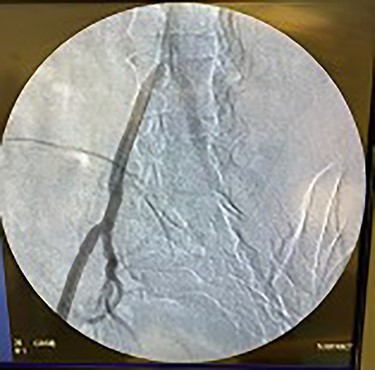

Catheter arteriogram results showed significant occlusion of the left iliac artery (Figs 3 and 4), the right iliac artery (Fig. 1), as well as the distal abdominal aorta (Fig. 2). There were numerous collateral vessels noted, indicating the presence of long-standing proximal stenosis (Fig. 1). The decision was made to use angioplasty to help widen the areas of stenosis. An 8 mm × 40 mm Passeo balloon was advanced from the right femoral artery into the left iliac artery (Fig. 7) and insufflated to 6 mmHg (Fig. 6). The balloon was allowed to remain expanded for 1 min and then was deflated. Next, the distal aorta was repaired in a similar fashion. The balloon was advanced into the distal aorta from the right femoral access and insufflated to 12 mmHg (Fig. 8). The balloon was allowed to remain expanded for 90 s.

Fluoroscopy of right iliac artery showing vast collateral vascular formation, indicating long-standing proximal obstruction.